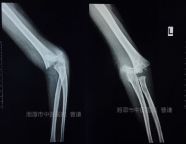

外院拍片情况如下:

复位固定后拍片情况如下:

治疗一个月后复查情况如下:

治疗近两个月复查情况如下: